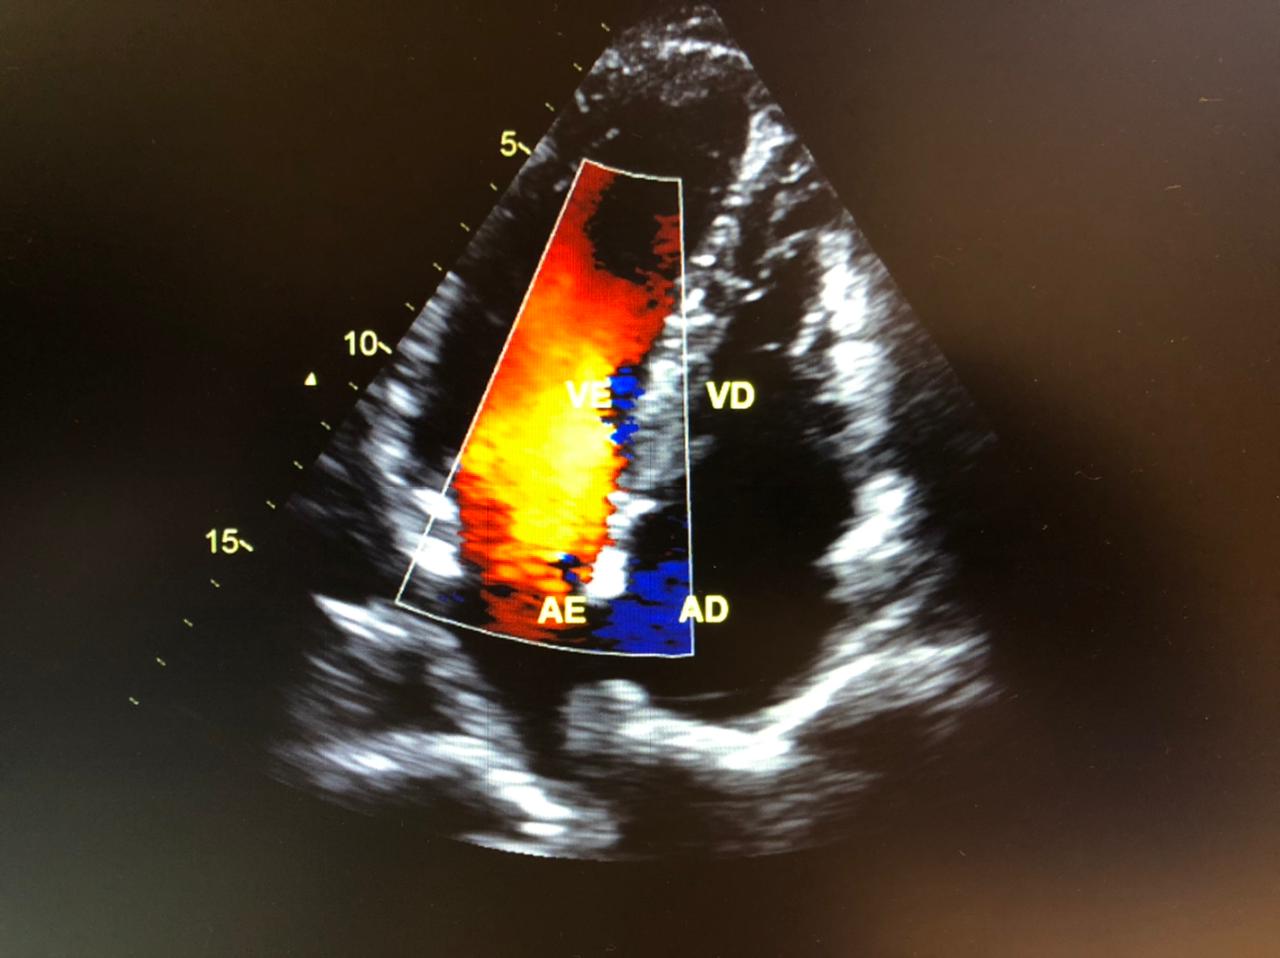

Quando o médico precisa de dados mais específicos sobre o fluxo de sangue e sua circulação pelas veias e artérias, é utilizado o ecocardiograma com doppler colorido.

As cores mostradas no exame ajudam a ter detalhes completos sobre a direção e a velocidade da circulação.

© Clínica ADS, 2021